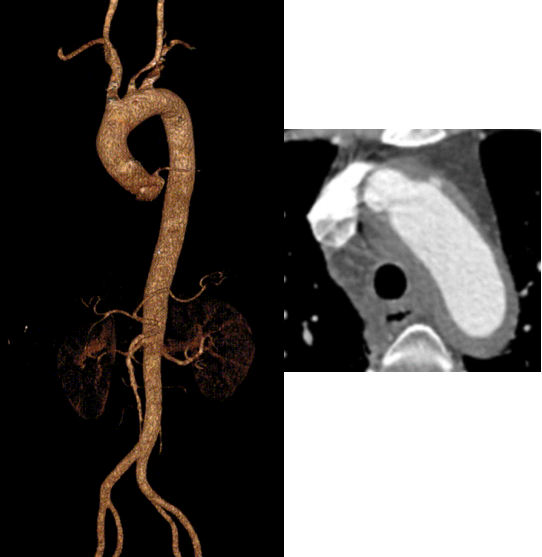

★ 病例2:模块内嵌分支胸主动脉覆膜支架系统

术前

术后